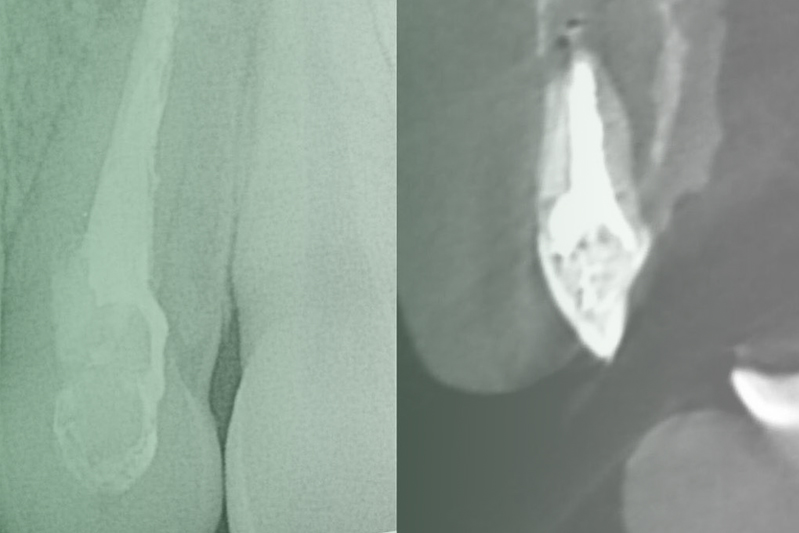

Клинический случай. Эндодонтия